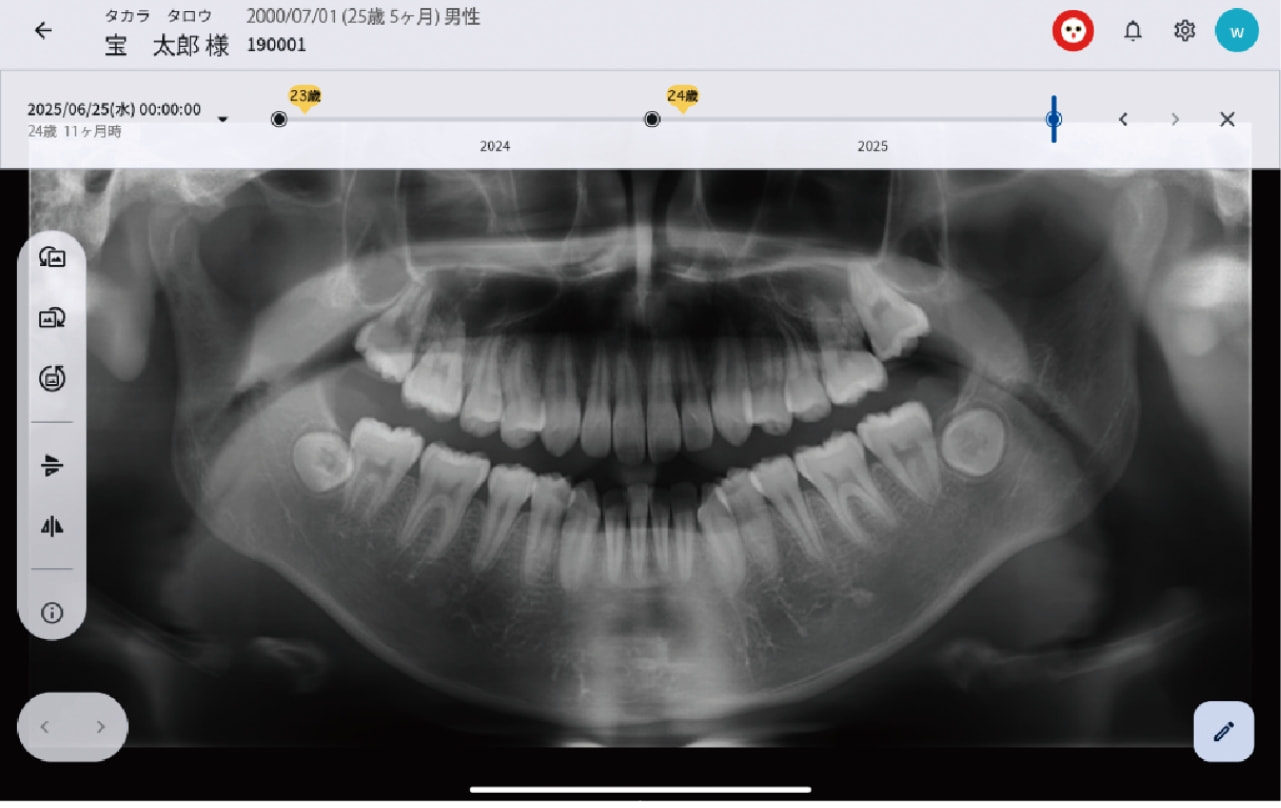

タイムライン表示

過去から現在までの口腔内データを時系列で追跡し、変化の積み重ねを“見える化”することで、診断はもちろん、予防・メンテナンスの説明も支援します